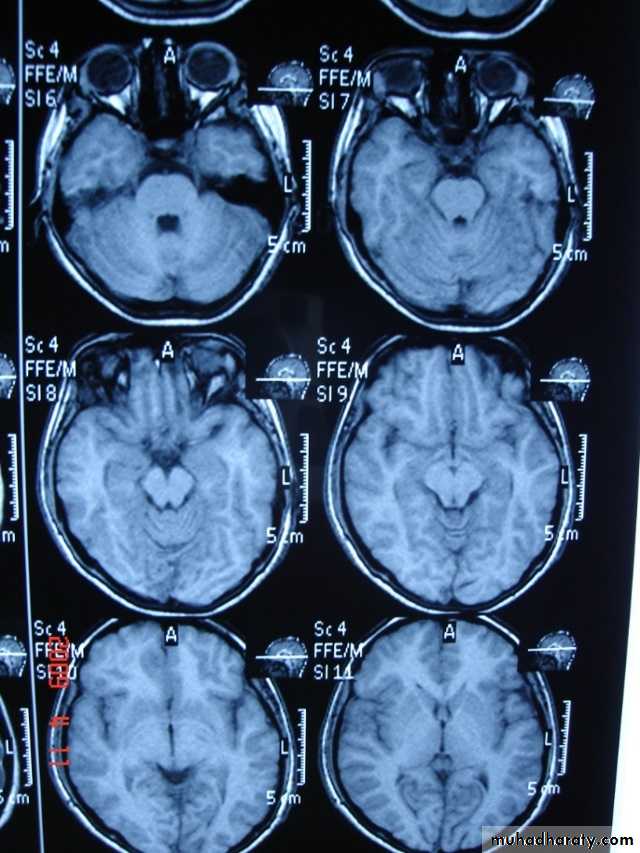

Coronal T1-weighted MRI image through a brain lesion showing homogeneity of the lesion, lack of a perceptible wall, lack of internal complexity, and CSF signal intensity. There is associated remodeling of the adjacent calvarium and brain displacement. These imaging features are typical of an arachnoid cyst.